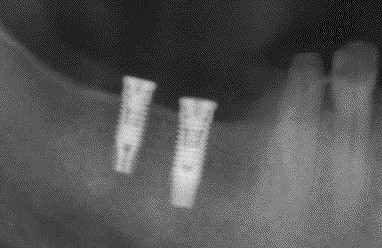

インプラントの術前・術後 Nさん